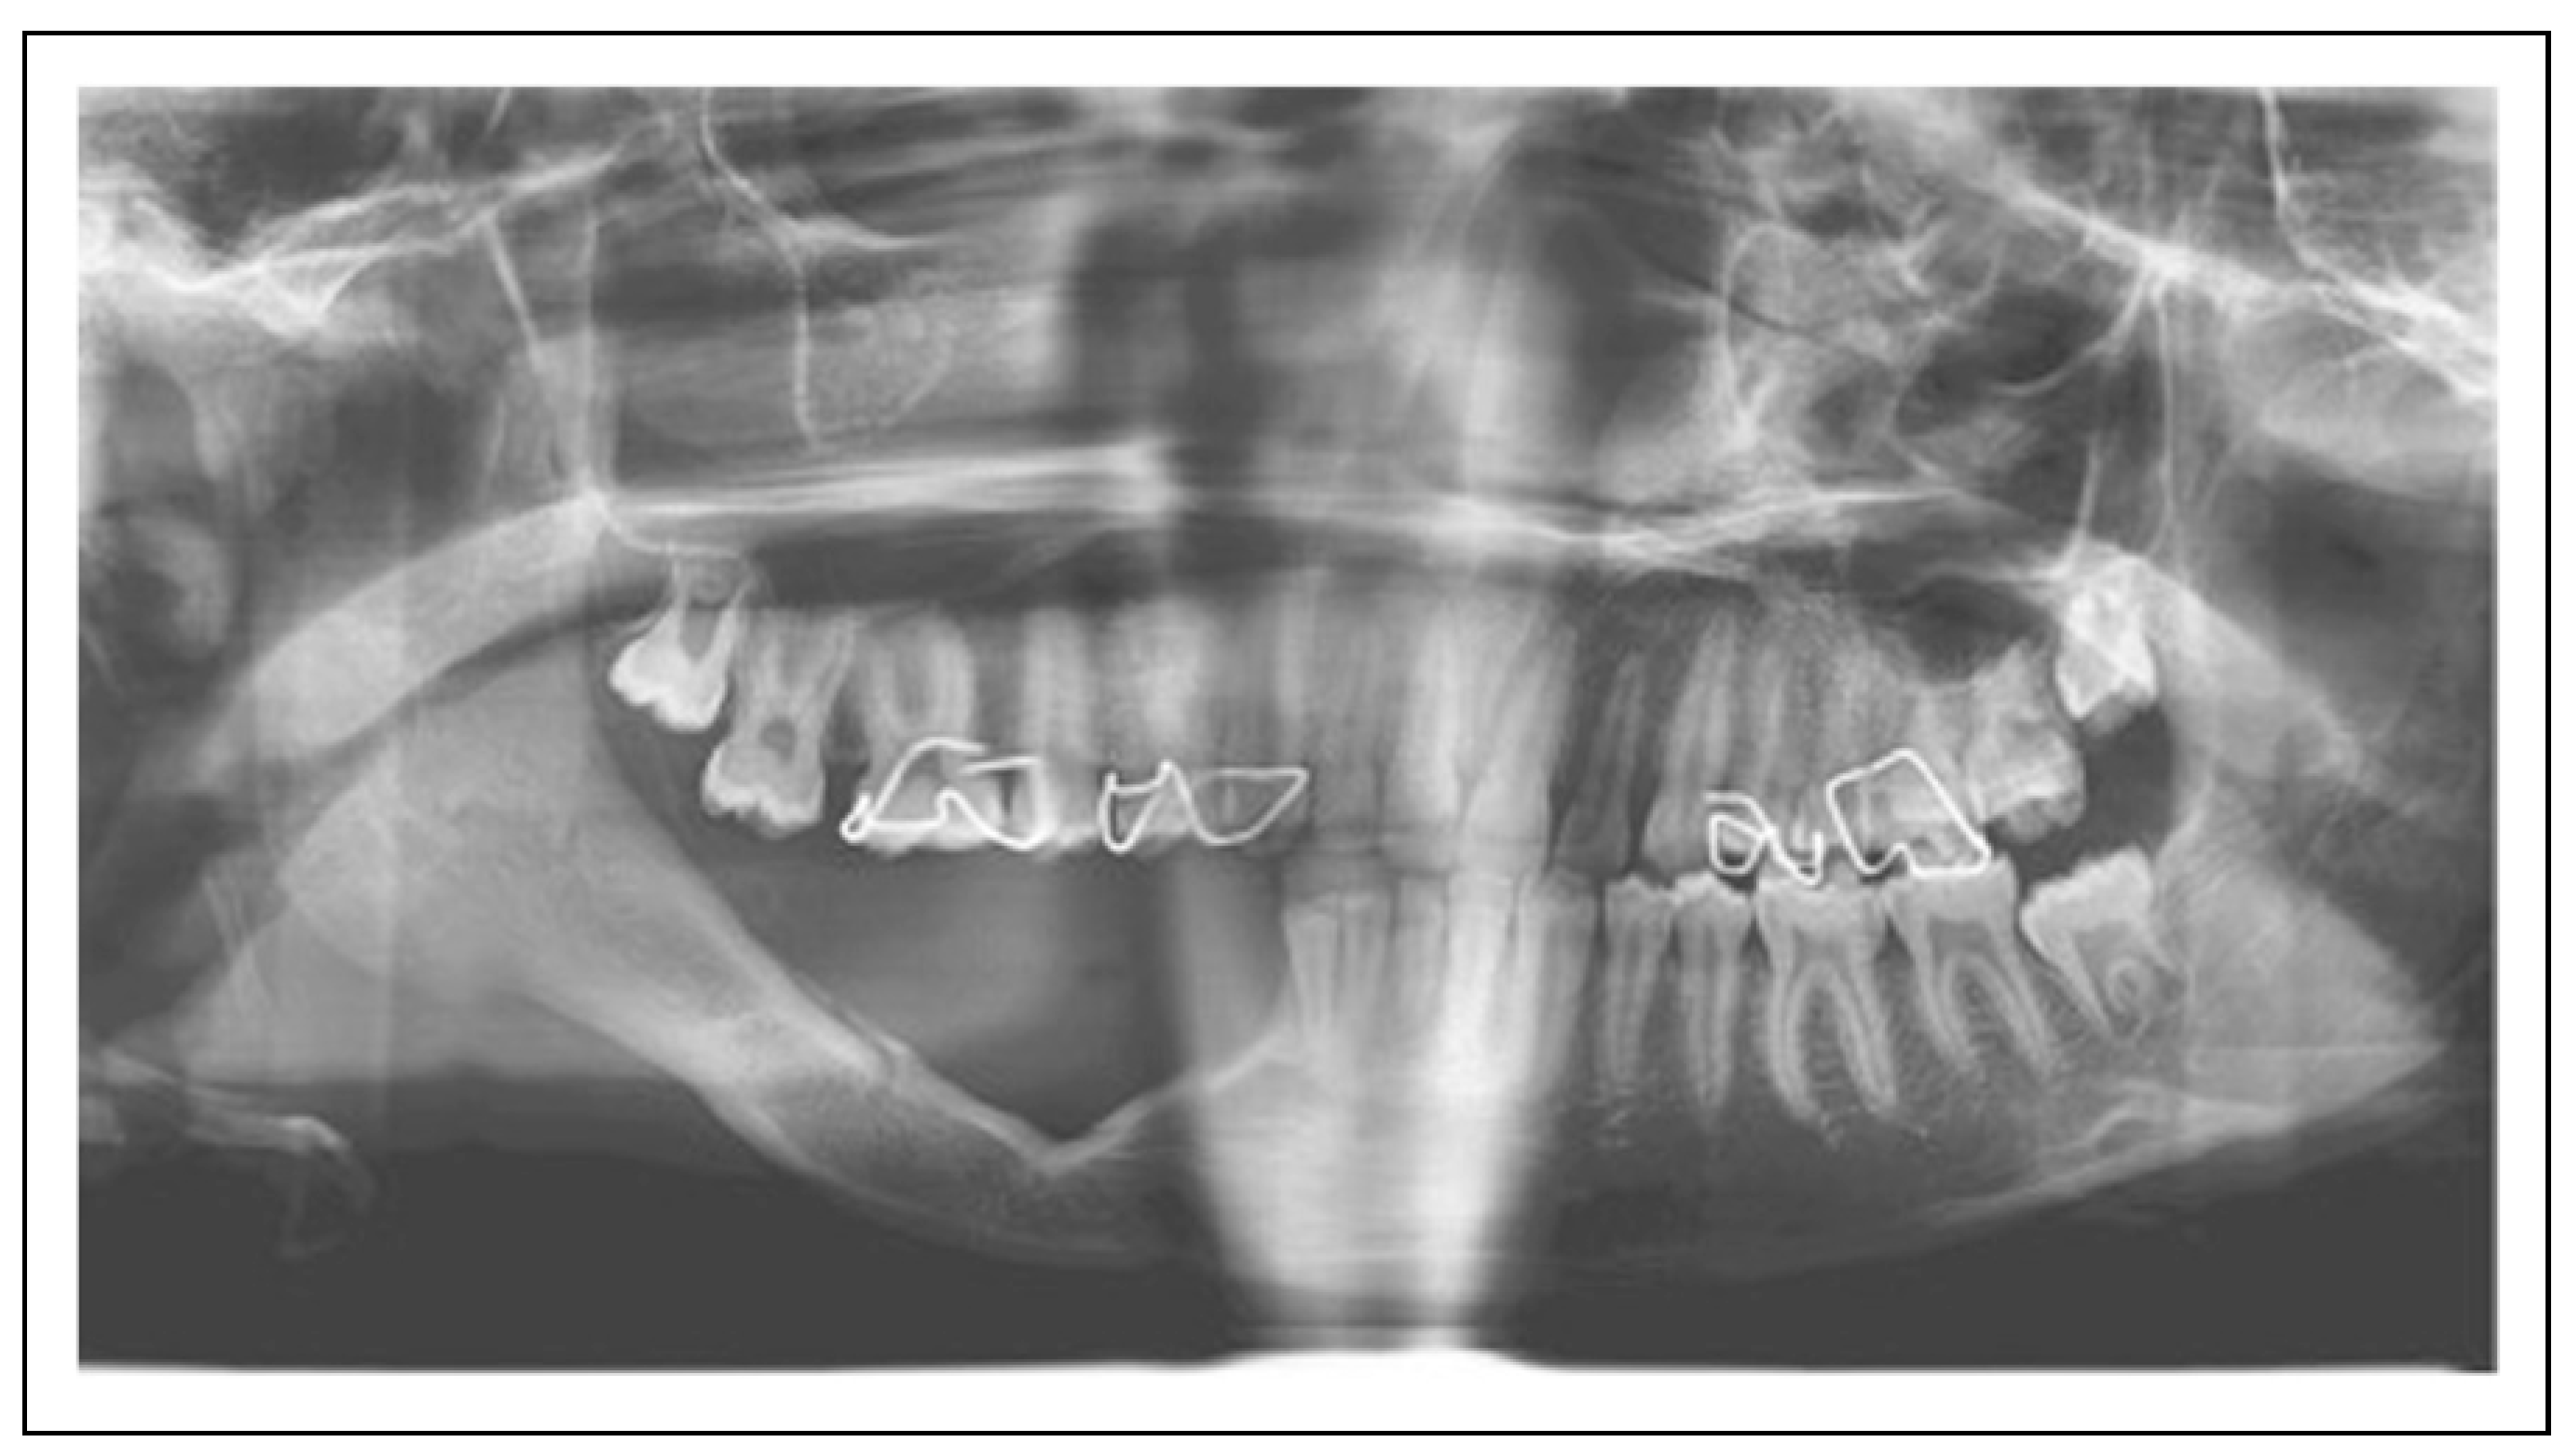

- Okoturo, E.; Ogunbanjo, O.V.; Arotiba, G.T. Spontaneous regeneration of the mandible: An institutional audit of regenerated bone and osteocompetent periosteum. J Oral Maxillofac Surg. 2016, 74, 1660–1667. [Google Scholar] [CrossRef] [PubMed]

- Cardinal, L.; Dominguez, G.C.; Marodin, A.L.; Rau, L.H. Unusual spontaneous mandibular regeneration of a large defect followed by orthodontics, alveolar distraction, and dental implant rehabilitation: A 10-year follow-up. J Oral Maxillofac Surg. 2016, 74, 786–793. [Google Scholar]